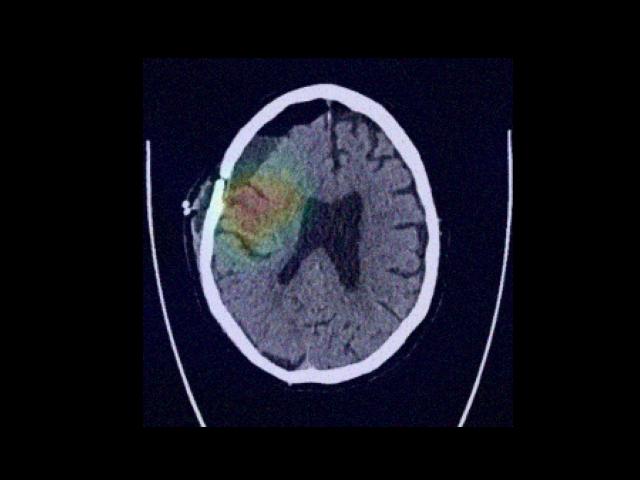

Sample Gallery